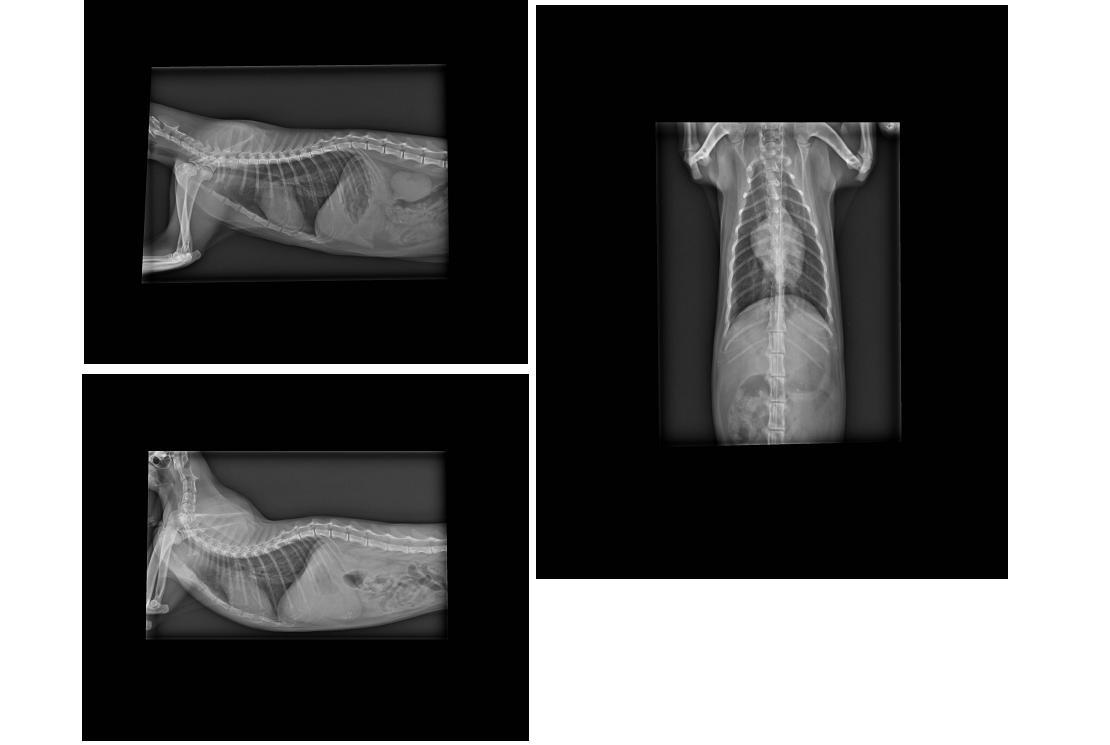

4.X-ray 400*3

送到醫院的小小有消瘦、脫水、不吃、流鼻膿(呼吸道感染),

且肝指數高,

所以趕緊上點滴治療後,

肝指數慢慢恢復正常。

原本食欲很好的小小,

在肝指數回復正常後,

仍不進食,故放置鼻胃管以灌食方式,

讓小小增加體力。

在王醫師團隊細心照料下,

小小終於恢復健康了!